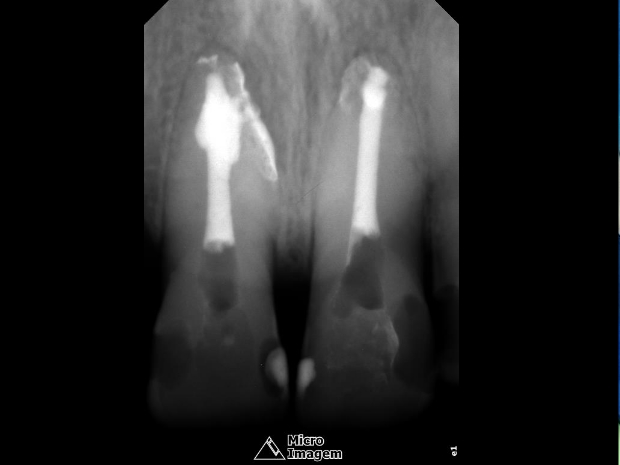

A obturação foi realizada pela técnica termomecânica Híbrida de Tagger (figuras 7 e 8) por meio do emprego de GutaCondensor (Maillefer/Suiça), cones de guta-percha TP (Dentsply/Brasil) e cimento obturador à base de M.T.A. Fillapex (Angelus/Brasil) (figura 9).

Após a termocompactação, realizou-se o corte da obturação, condensação vertical com o uso de calcadores a frio, limpeza da câmara pulpar e restauração provisória imediata do mesmo (figura 10). Observou-se radiograficamente selamento de ramificações e de áreas reabsortivas, bem como a presença de pós-operatório silencioso.

- Figura 7

- Figura 8